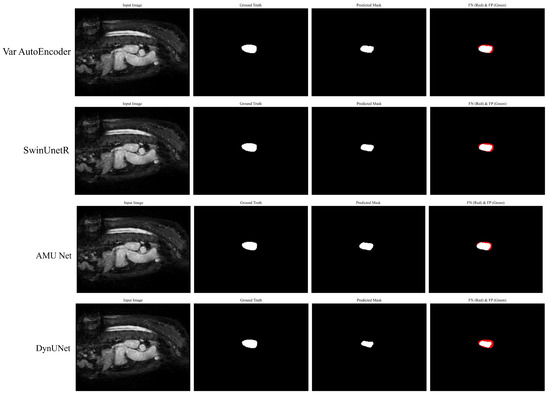

Figure 10 shows the visual comparison of segmentation results produced by our proposed AMU-Net model and four other top-performing models. The columns represent the input images, ground truth masks, predicted masks, and FN -FP areas. Our AMU-Net demonstrates superior segmentation performance which is closely aligned with the ground truth. It also shows lower FN and FP regions compared to the other models such as Var AutoEncoder, SwinUnetR, and DynUNet. This comparison highlights the effectiveness of our AMU-Net in accurately segmenting the target regions compared to other models.

Figure 10.

The visualization results of different models along with FP and FN.